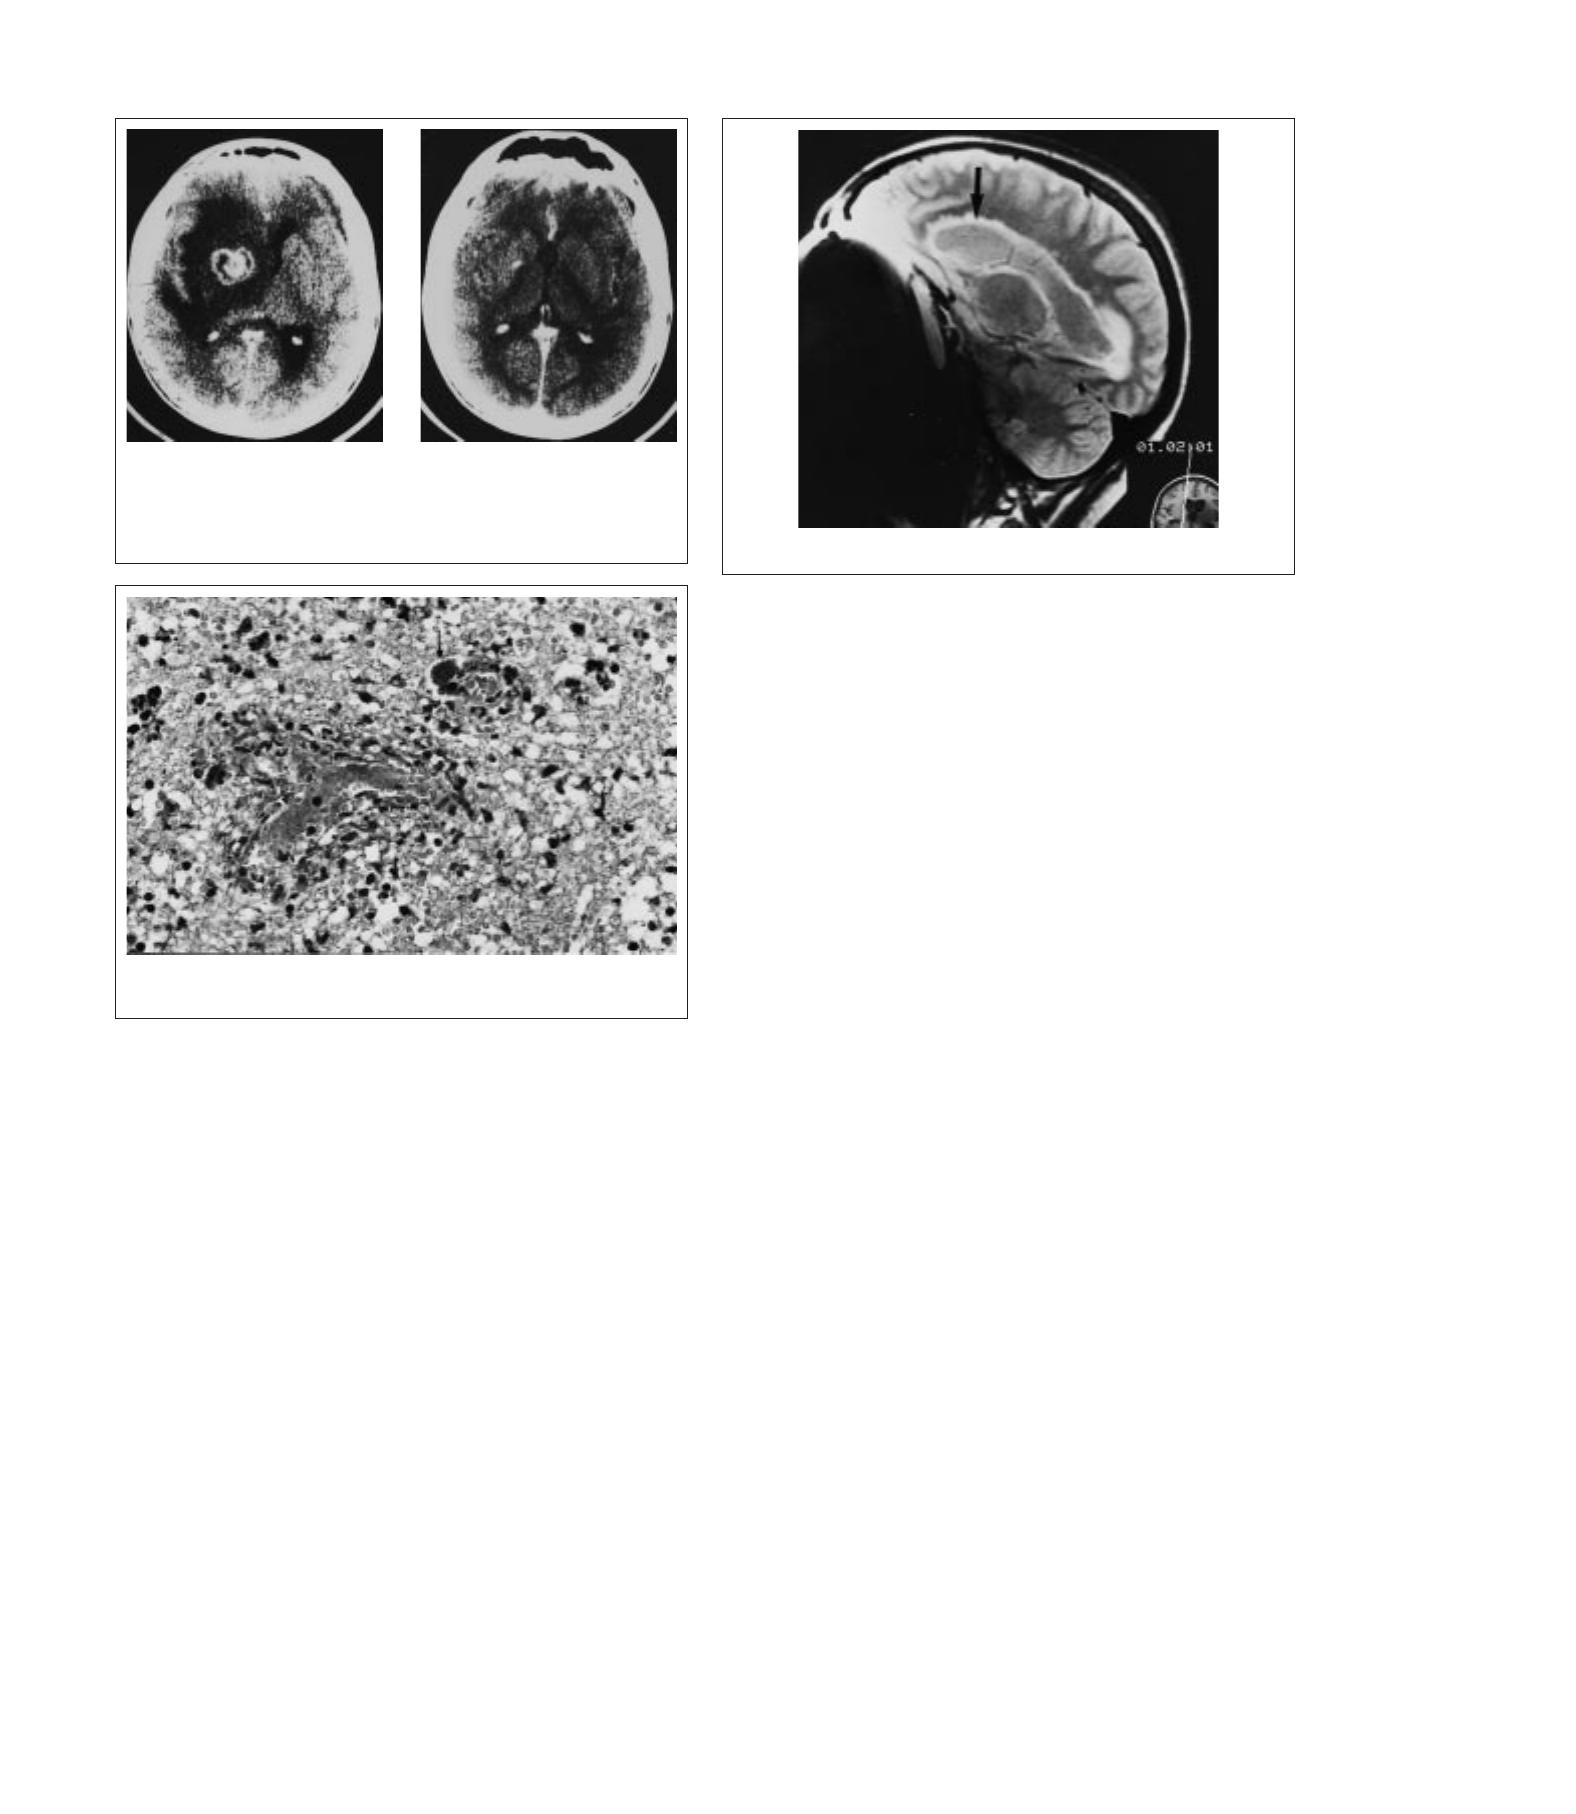

À côté des lésions encéphalitiques, des désordres vasculaires ne sont pas

exceptionnels chez les patients atteints du VIH, immunodéprimés ou non. Si

les accidents vasculaires ischémiques étendus sont rares chez ces patients,

leursurvenue chez un adulte jeunedoitfairerechercherunesyphilisquiinduit

souvent une artérite. Les séries autopsiques montrent un taux relativement

élevédelésionsischémiques,souvent multiples et depetite taille. Deslésions

des capillaires et petites artérioles sont observées, avec parfois un

épaississement massif de leur paroi occluant leur lumière (fig 4)

[55]

.De

micro-infarctus hémorragiques sont parfois rencontrés (fig 5). Enfin, des

infiltrats inflammatoires lymphocytaires sont très fréquents. On notera la

4Lésionsischémiqueschezunpatientatteintparlevirusdel’immunodéficiencehumaine.

Microangiopathieavecaspectfeuilletédescapillairesdubulbe(flèches).Coupeenparaffine

(hématéine-éosine, ×300).

5Microhématomes multi-

plesdanslecorpscalleuxetla

capsule interne.